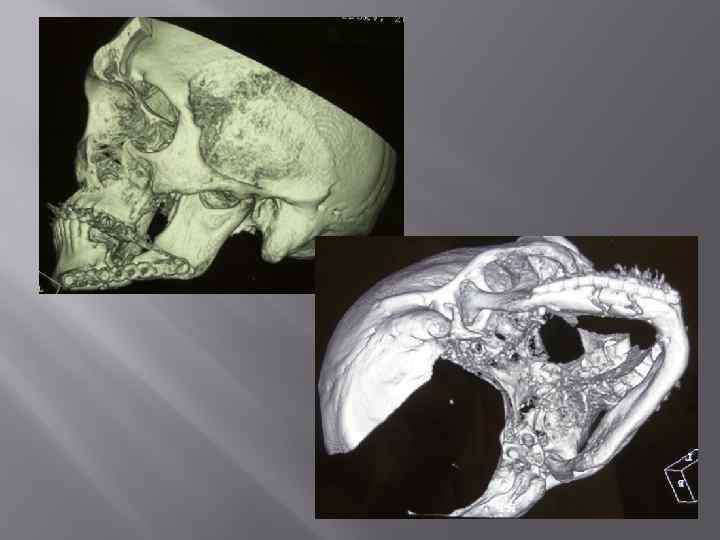

Перелом нижней челюсти. Травматический остеомиелит. Абсцесс поднижнечелюстной области справа. Некроз мягких тканей. Секвестрация костной ткани.